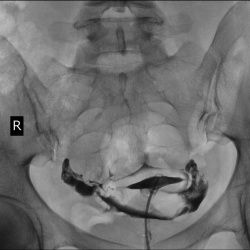

Женщины, желающие стать матерями. Облучаем. По сжатой программе.

#1. Вариант расположения матки. И нормальны придатки.